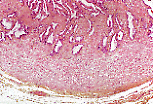

黏膜具有细长的初级皱襞,初级皱襞上又布满常相互吻合的次级和三级皱襞,

形成呈蕾丝状、迷宫样的腔隙。

精囊黏膜上皮由相对高柱状的细胞构成,细胞顶部无明显分化,胞质中可含脂褐素色素。

该色素在本标本中不可见,其含量随年龄增长而增加,使上皮呈现赭石色。